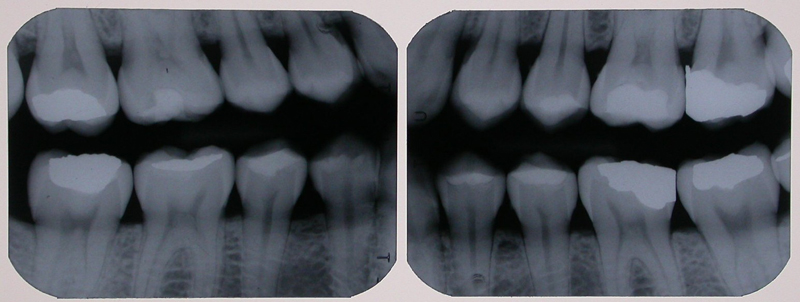

Radiografia Interproximal

O objetivo principal desta técnica é o exame das faces proximais dos dentes posteriores e da crista óssea alveolar. É indicado na detecção de processos cariosos, adaptações marginais de restaurações e presença de lesões periodontais, que apresentem comprometimento de estruturas ósseas, com destruição da crista óssea alveolar.